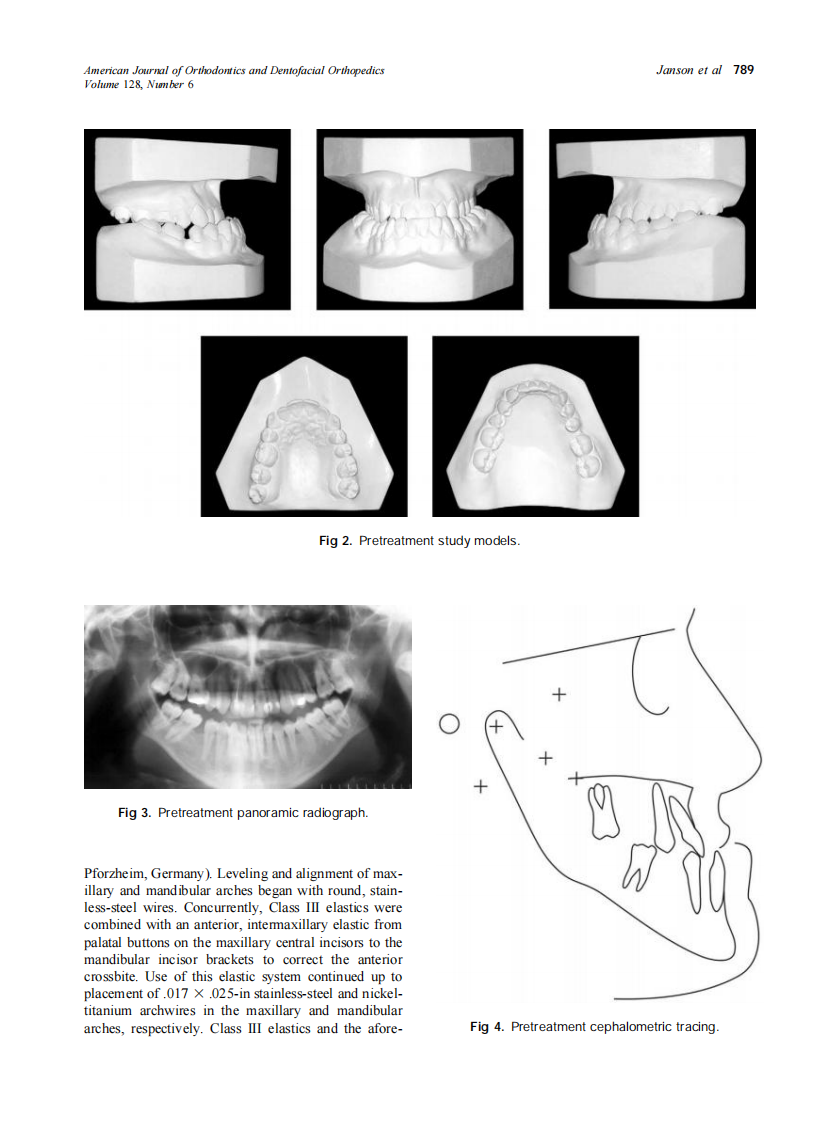

2005_128_6_787_794_Janson.pdf